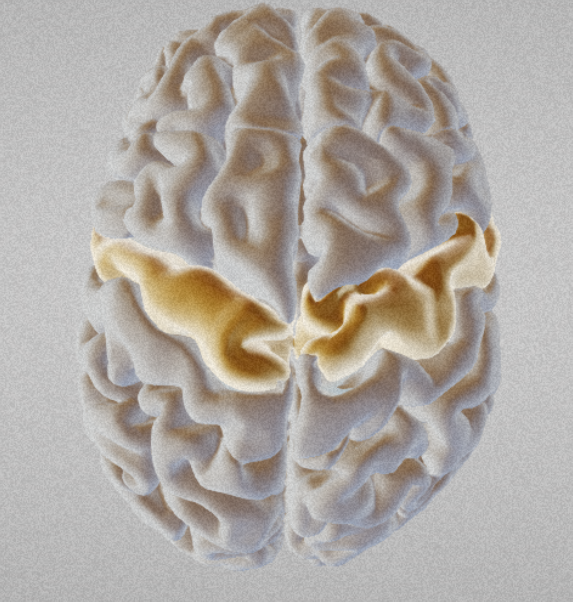

Cingulate gyrus

Sylvian fissure

Precentral gyrus (primary motor cortex)

Precentral gyrus (primary motor cortex)

Postcentral gyrus